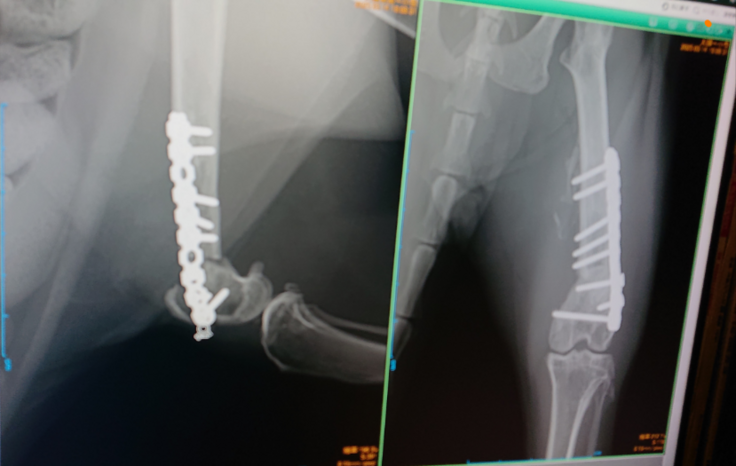

事故による大腿骨骨折のじん♂